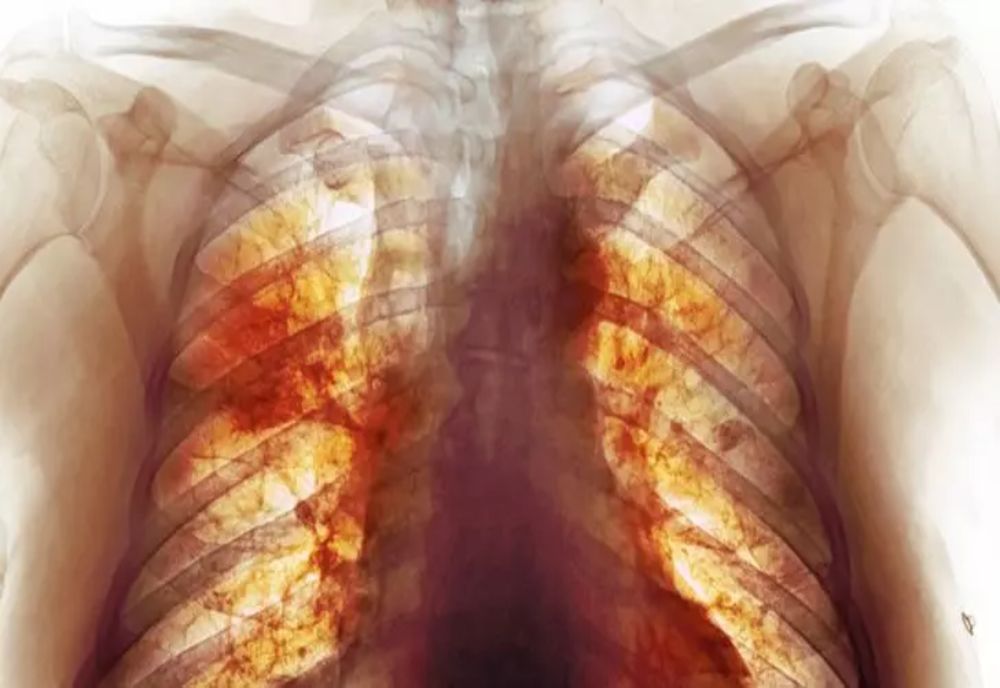

3 feb. 2022, 07:33ActualitateAdevărata dimensiune a dezastrului Covid. Cea mai detaliată radiografie dezvăluie cum arată, de fapt, plămânii după infectare - FOTO